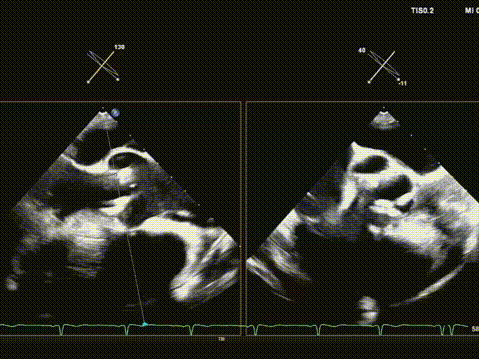

超声引导导丝跨瓣成功;

确认导丝在心尖部;

22mm球囊预扩;

输送系统顺利过弓及跨瓣;

快速起搏下初次释放瓣膜,瓣膜开口形态不好,位置偏高;

遂回收瓣膜,重新跨瓣并调整瓣膜释放位置后;

快速起搏下再次释放瓣膜至工作位,超声评估开口形态可,位置深度满意;

遂150快速起搏下完全释放瓣膜;

观察无瓣膜移动,回撤导丝后撤出系统;

术后超声评估,瓣膜位置深度满意,形态可,微量瓣周漏,最大血流速度1.53m/s,平均跨瓣压差4mmHg。